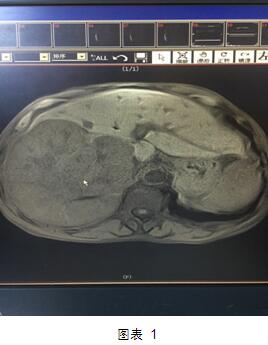

但是近日,我院肝膽外科就做了一次這樣的大挑戰(zhàn)?;颊呤且晃?0多歲的老者,老人家入院后診斷為肝右葉巨塊型肝癌(圖1)。這個癌塊已經(jīng)占據(jù)整個肝臟的60%,而且腫瘤侵及第一肝門、第二肝門,門靜脈有癌栓形成。這種情況在臨床上已經(jīng)屬于中晚期肝癌,手術(shù)根治困難,風(fēng)險極大。然而不手術(shù)切除的話,老人家的生存期恐怕不會超過三個月,而且會一直處于癌癥的折磨之中。